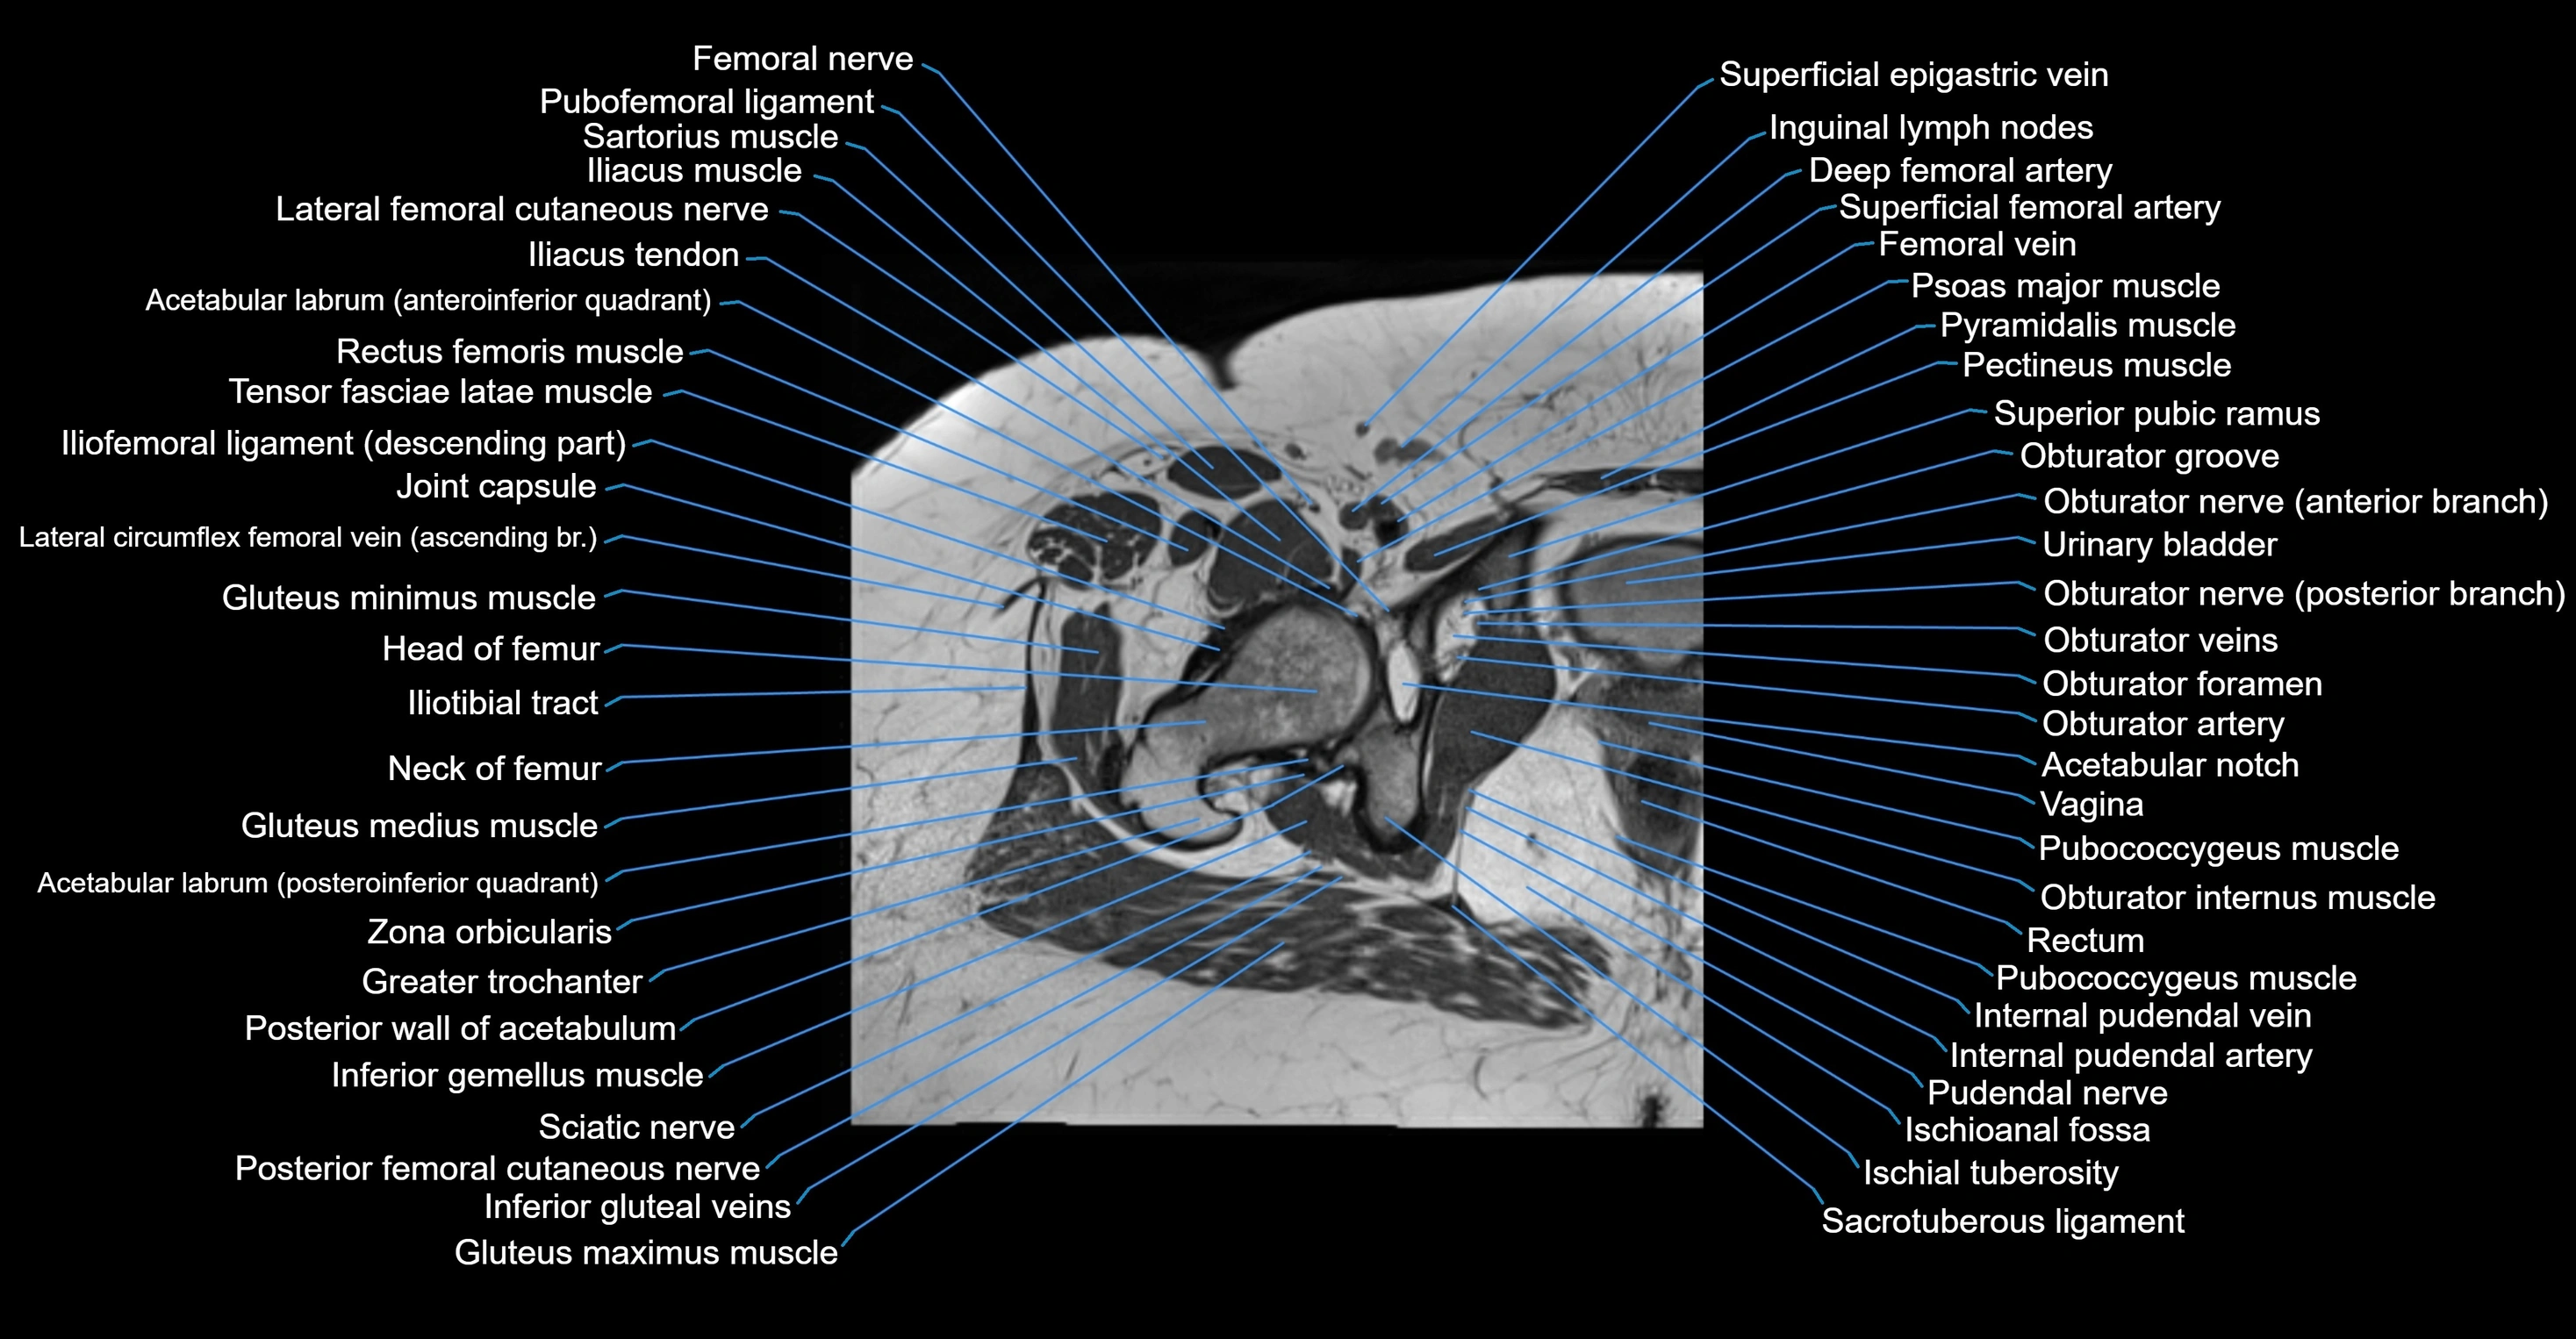

- Acetabular labrum

- Acetabular notch

- Head of femur

- Hip joint

- Neck of femur

- Obturator foramen

- Obturator internus muscle

- Obturator nerve

- Obturator vein

- Obturator veins

- Pubofemoral ligament

- Rectum

- Urinary bladder

- Vagina

- Zona orbicularis ligament